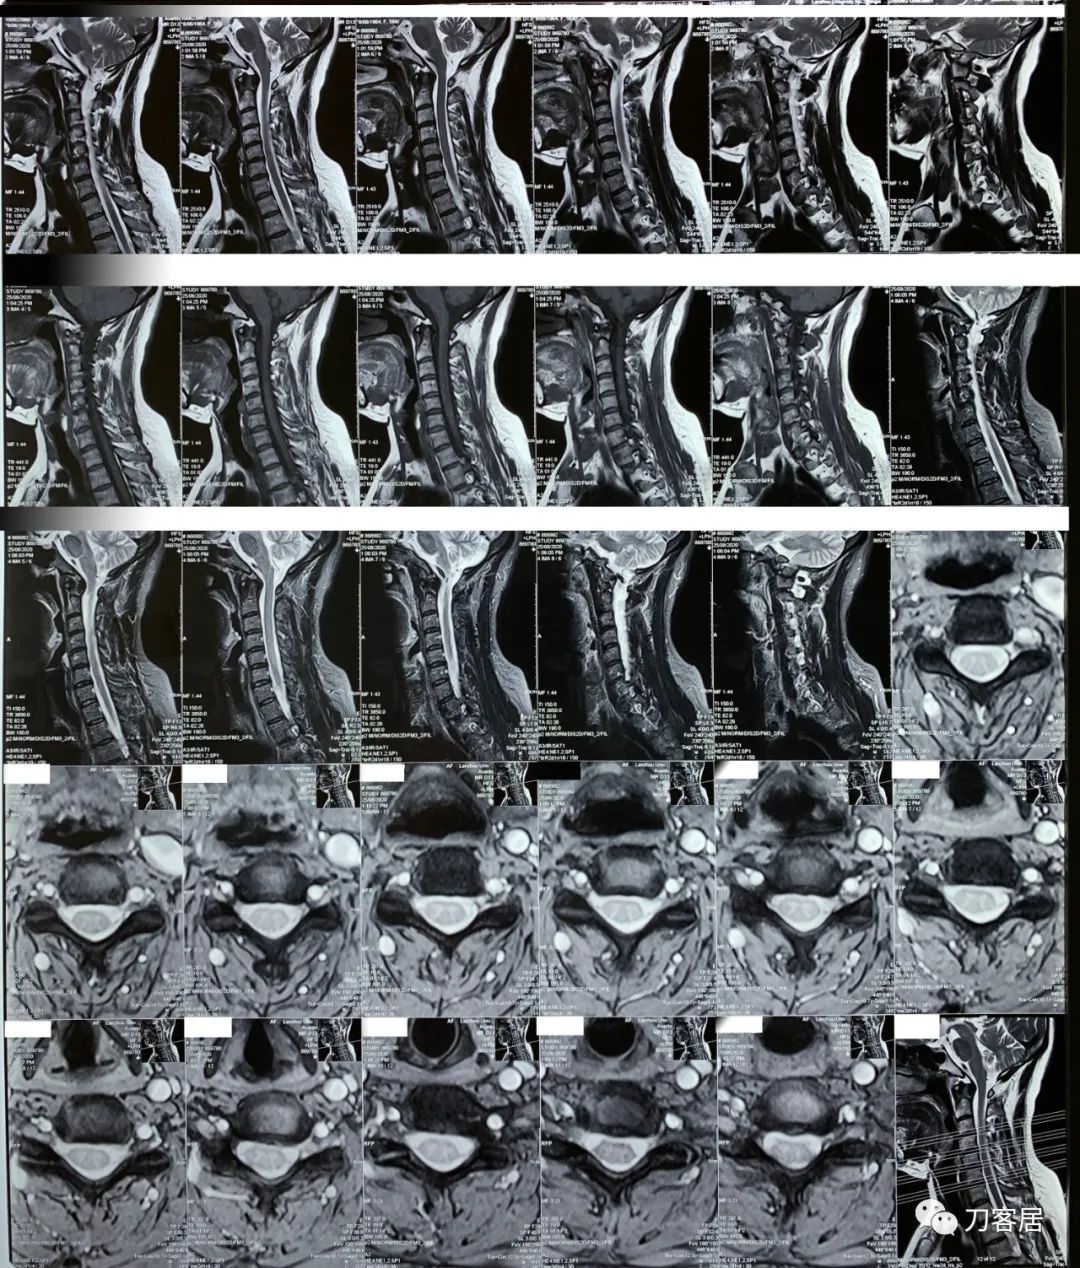

患者自2020年8月4日始头晕,2020年8月25日双手麻,双胳膊麻,于兰大二院定西分院检查颈椎MRI及腰椎X线片, 提示1. 颈椎生理曲度变直,2. 颈椎骨质增生,3. 颈椎间盘变性,颈4-7椎间盘轻度膨隆,4. 腰椎侧弯畸形。

从这个患者的影像资料分析,颈椎间盘突出问题不大,没有明确的上位神经元损伤表现,所以,不考虑颈椎和胸椎问题。腰椎侧弯畸形,但不严重。因为存在腰椎侧弯,使得腰椎MRI在扫描切面的时候,显示的椎间盘突出或椎管狭窄会有一定的误差,所以,又加做了经椎间盘的CT平扫,影像表现并不严重,综上,腰椎间盘突出,腰椎管狭窄,腰椎侧弯,不考虑手术治疗。同时,患者的主要痛苦是心理疾病,而不是器质性疾病,所以,以心身疾病治疗为主。虽然患者骨密度检查结果提示正常,但X线片显示骨质疏松,且其症状也与骨质疏松的症状有符合之处,比如静息痛,不能入睡,动作及姿势变换时痛加重等,所以,给予实验性抗骨质疏松治疗,以观疗效。

1. 2020年8月4日因头晕,就诊于兰大二院定西分院,颈椎MRI检查提示颈椎生理曲度变直,颈椎骨质增生,颈椎间盘变性,颈4-5,颈5-6,颈6-7椎间盘轻度膨隆,相应层面硬膜囊受压

2. 2020年8月25日在兰大二院定西分院因手麻,胳膊麻,做了颈椎核磁检查